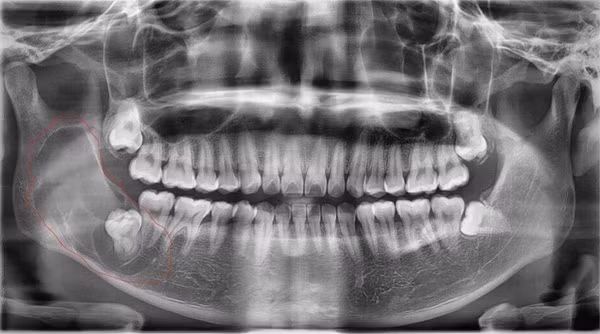

Hình ảnh chụp X-quang cho thấy bệnh nhân có năng răng sừng hoá rất to ở góc hàm phải kèm theo 1 răng số 8 đâm ngang phía đối diện

Kết quả cho thấy, bệnh nhân bị nang răng sừng hoá (hay còn gọi nang răng sinh sừng). Trường hợp bệnh nhân này nang rất lớn, phát triển từ răng số 7 lan lên tới tận xương hàm trên.